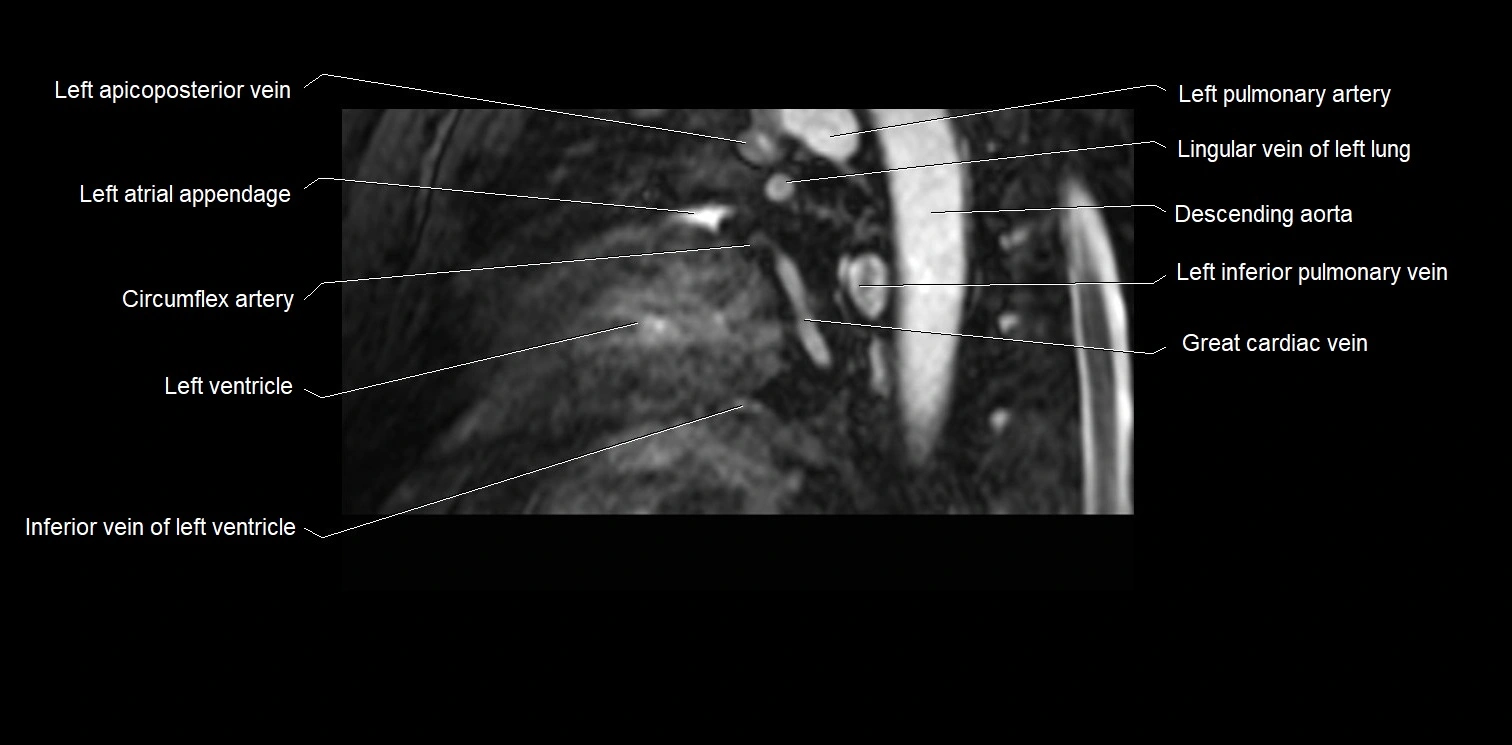

MRI image